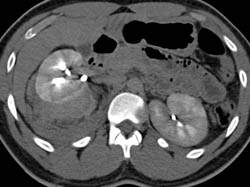

Renal Cell Carcinoma Simulates A Transitional Cell Cancer (TCC)